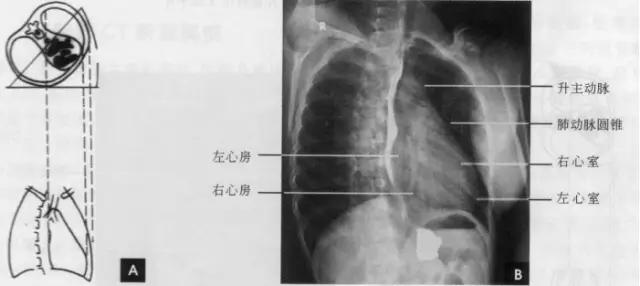

(一)后前位 正常心影2/3位于中线左侧,1/3位于右侧,心尖指向左下,心底部朝向右后上方,形成斜的纵轴。后前位心脏大血管有左右两缘:心右缘分为两段,上段为升主动脉与上腔静脉的总合影,在幼年和青年人边缘主要为上腔静脉影向上延伸,在老年人常见纡曲延长的升主动脉影突出于上腔静脉边缘之外;心右缘下段为右心房所构成,有时在心瞩角内可见一向外下方倾斜的三角形影,为下腔静脉攻肝静脉影,深吸气时明显。心左缘分为三段,上段为主动脉弓;中段为肺动脉主干,但偶尔可为左稀动脉构成,称肺动脉段或心腰,此段较低平或稍突出:下段由左心室构成,左心室在下方形成心尖。左心室与肺动脉之间有长约10cm的一小段,由左心耳构成,正常时不能与左心室区分。透视下左心室与肺动脉段的搏动方向相反,两者的交点称相反搏动点,该点上下两侧心缘里“翘翘板”样运动,该点位置是衡量左右心室增大的一个重要标志。肥胖人左心膈角常有脂肪垫充填,为密度较低的软组织影。后前位能了解心胸及肺循环概况,正常人心(h1+h2)胸(t)比率不大于0.5(如下图)。

标准右前斜位(又称第一斜位)为后前位向左旋转约45。所得影像。心前缘自上而下由主动脉弓曼升主动脉、肺动脉、右心室漏斗部、右心室前壁和左心室下端构成。升主动脉前缘平直,弓部则在上方弯向后行;肺动脉段和漏斗部稍为隆起;心尖以上大部分为右心室构成。心前缘与胸壁之间有尖向下的三角形透明区称为心前间隙。心后缘上段为左心房,下段为右心房,两者无清楚分界。心后缘与脊柱之间透明区称心后间隙,食管在心后间隙通过,钡剂充盈时显影。右前斜位主要观察右室流出道及左心房大小(如下图)。

(三)左前斜位 从后前位向右旋转约60。得到左前斜位(又称第二斜位).此时室间隔与中心x线接*平近**行。因此.两个心室大致是对称的分为两半,前方一半为右心室.后方一半为左心室。心前缘上段为右心房.下段为右心室,右心房段主要由右心耳构成,房室分界不清。右心房影以上为升主动脉,两者相交成钝角:心后缘可分为上下两段,上段由左心房,下段则由左心室构成。左心室段的弧度较左心房大,两个不同弧度的交接点,可作为两者的分界。通过主动脉窗可兄气管分叉,主支气管和肺动脉,左主支气管下方为左心房影。左前斜位可了解各房室和主动脉情况(如下图)。

(四)左侧位 心影从后上向前下倾斜,心前缘下段为右心室前壁,上段则由右心室漏斗部与肺动脉主干构成,再苣上为升主动脉前壁,直向上走行。这些结构与翦髓壁之间的三角形透亮区称为胸骨后区。心后缘上中段由左心房构成,下段则由左心室构成。心后下缘、食管与膈之间的三角形间隙,为心后食管前间隙(如下图)。